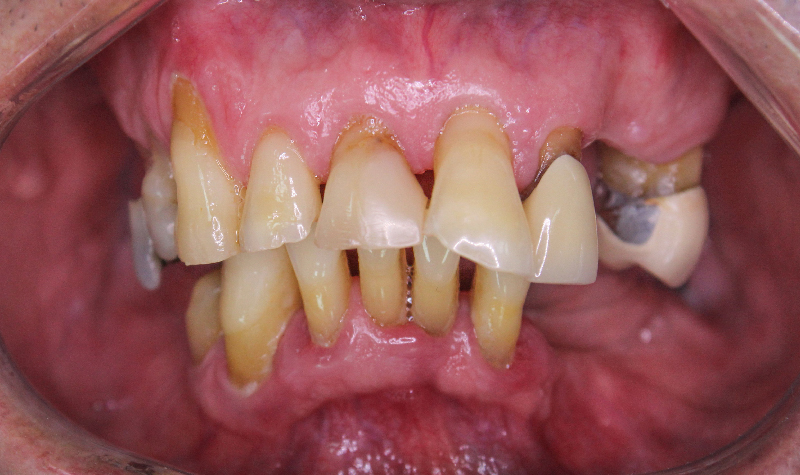

Rehabilitación oral total de alta complejidad con cerámicas sobre dientes e implantes.